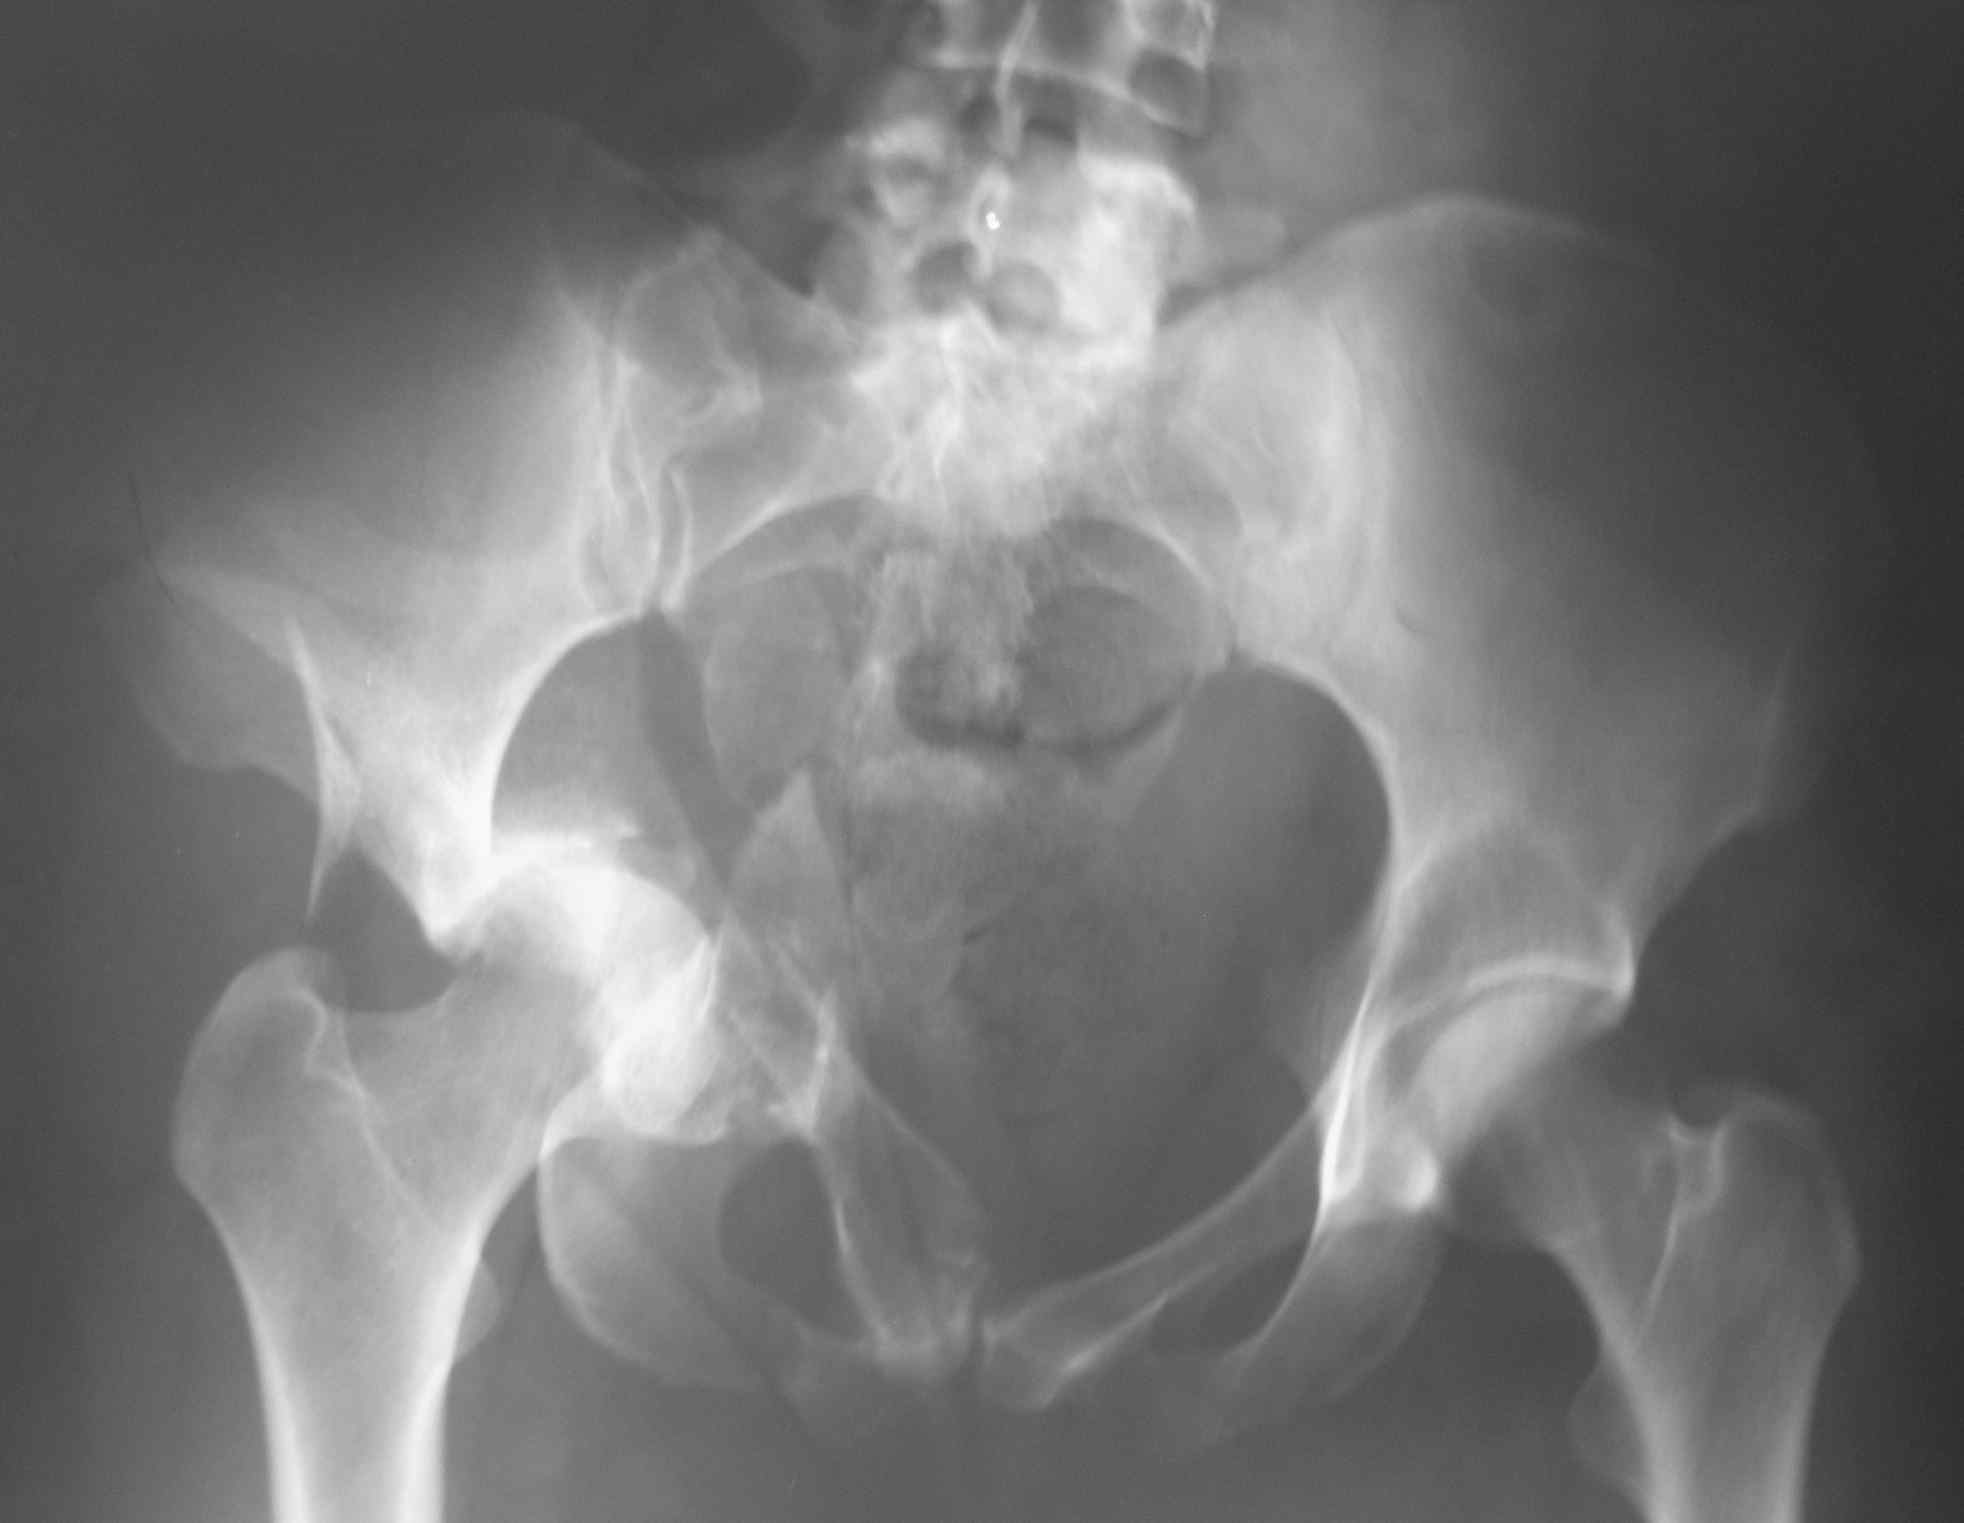

Большое спасибо за содержательные советы. Вот снимок при поступлении.

К сожалению, даже по представленным рентгенограммам видно, что ничего особенного после так называемого Вами вправления не изменилось. Если сделать КТ или МРТ картина будет ещё более удручающей. Прочитайте внимательнее пост Батала Алексеевича Шушании и прислушайтесь к его совету, потому, что время данной ситуации работает против пациента.

"перед выбором, либо идти на открытое вмешательство и восстанавливать переднюю колонну, либо продолжить вытяжение до консолидации переломов с последующей костной пластикой и эндопротезированием"

На основании одной проекции трудно определить к какому перелому вертлужной впадины относится данный перелом, тем более подсказать "подвздошно бедренный доступ, хотя можно и из бокового чрезвертельного" оперативный доступ. Нужны обязательные стандартные рентген снимки по Judet: прямой и косые снимки, из косых запирательный и подвздошные снимки ацетабулума. Рентген снимки и Компьютерную Томограмму лучше сделать после скелетнего вытяжения.

Все переломы ацетабулума являются серезными внутрисуставными переломами и от своевременной правильной помощи зависит судьба сустава. Квалицированная срочная операция, особенно молодым, спасет от раннего эндопротезирования.